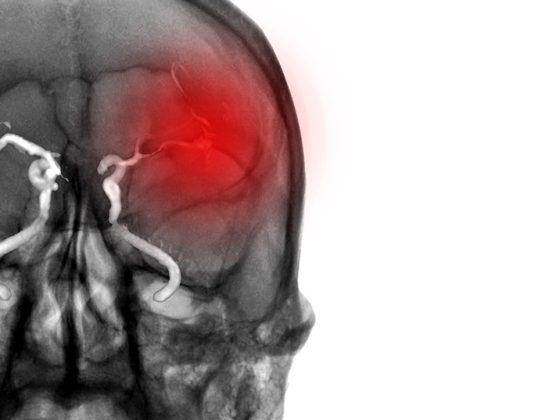

Nach der Menopause ist bei Frauen das Ausmass bestimmter Hirnschäden grösser als bei gleichaltrigen Männern. Zu diesem Schluss kommen Forschende des Deutschen Zentrums für Neurodegenerative Erkrankungen (DZNE) aufgrund der Untersuchung von mehr als 3.400 Erwachsenen im Rahmen der Bonner Rheinland Studie. Die untersuchten Gewebeschäden gelten als mögliche Risikofaktoren für Demenz und Schlaganfall. Die aktuellen Befunde unterstreichen die Bedeutung einer geschlechtsspezifischen Medizin.